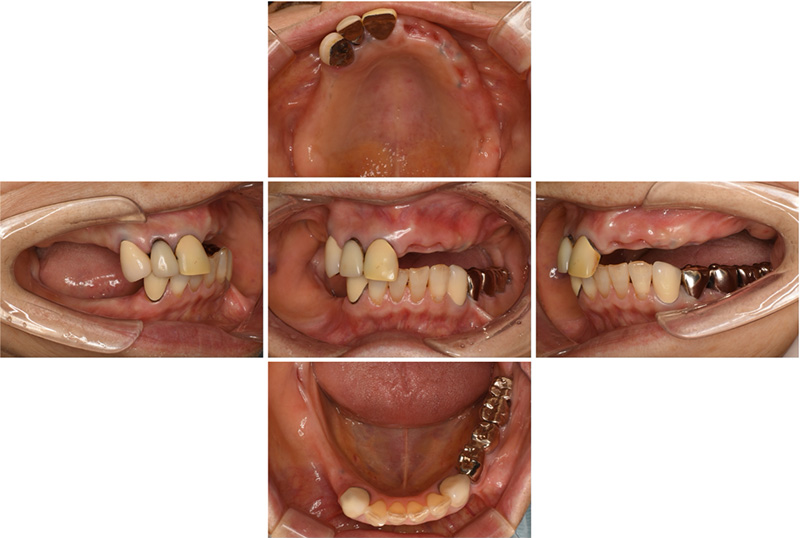

46歳女性

治療前